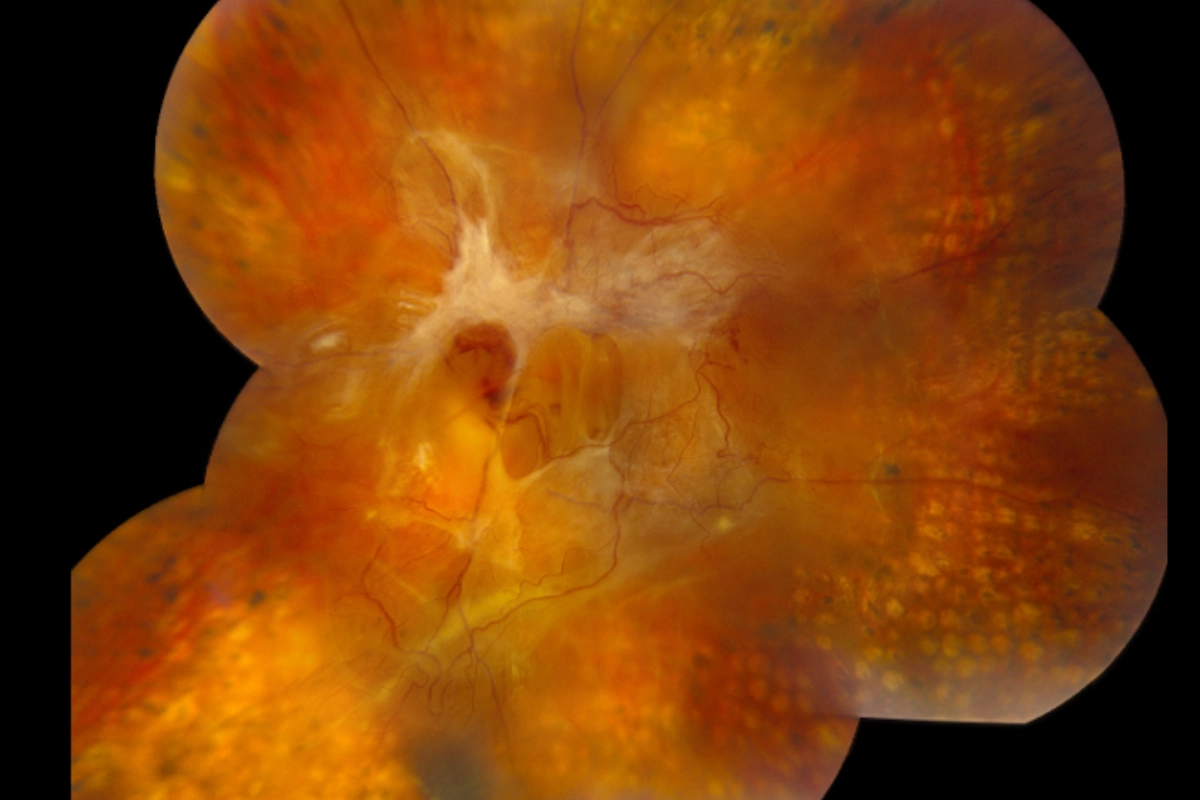

Diabetic retinopathy is damage to the blood vessels of the retina caused by chronically elevated blood sugar. Over time, those vessels weaken, leak fluid, and can close off entirely — depriving the retina of oxygen and triggering the growth of abnormal new blood vessels. It is the leading cause of preventable blindness in working-age adults in the United States.

There are four main stages. Mild NPDR is the earliest, characterized by small microaneurysms in the retinal vessels. Moderate to severe NPDR involves more widespread vessel damage and blockage. Proliferative diabetic retinopathy (PDR) is the most advanced stage, marked by the growth of fragile new blood vessels that bleed easily and can cause retinal detachment. Diabetic macular edema can occur at any stage and is the most common cause of vision loss in diabetic patients.

Diabetic macular edema occurs when fluid leaks from damaged retinal blood vessels into the macula — the central part of the retina responsible for sharp, detailed vision. The macula swells, causing blurry or distorted central vision. DME can develop at any stage of diabetic retinopathy and requires prompt evaluation and coordinated care with a retina specialist.